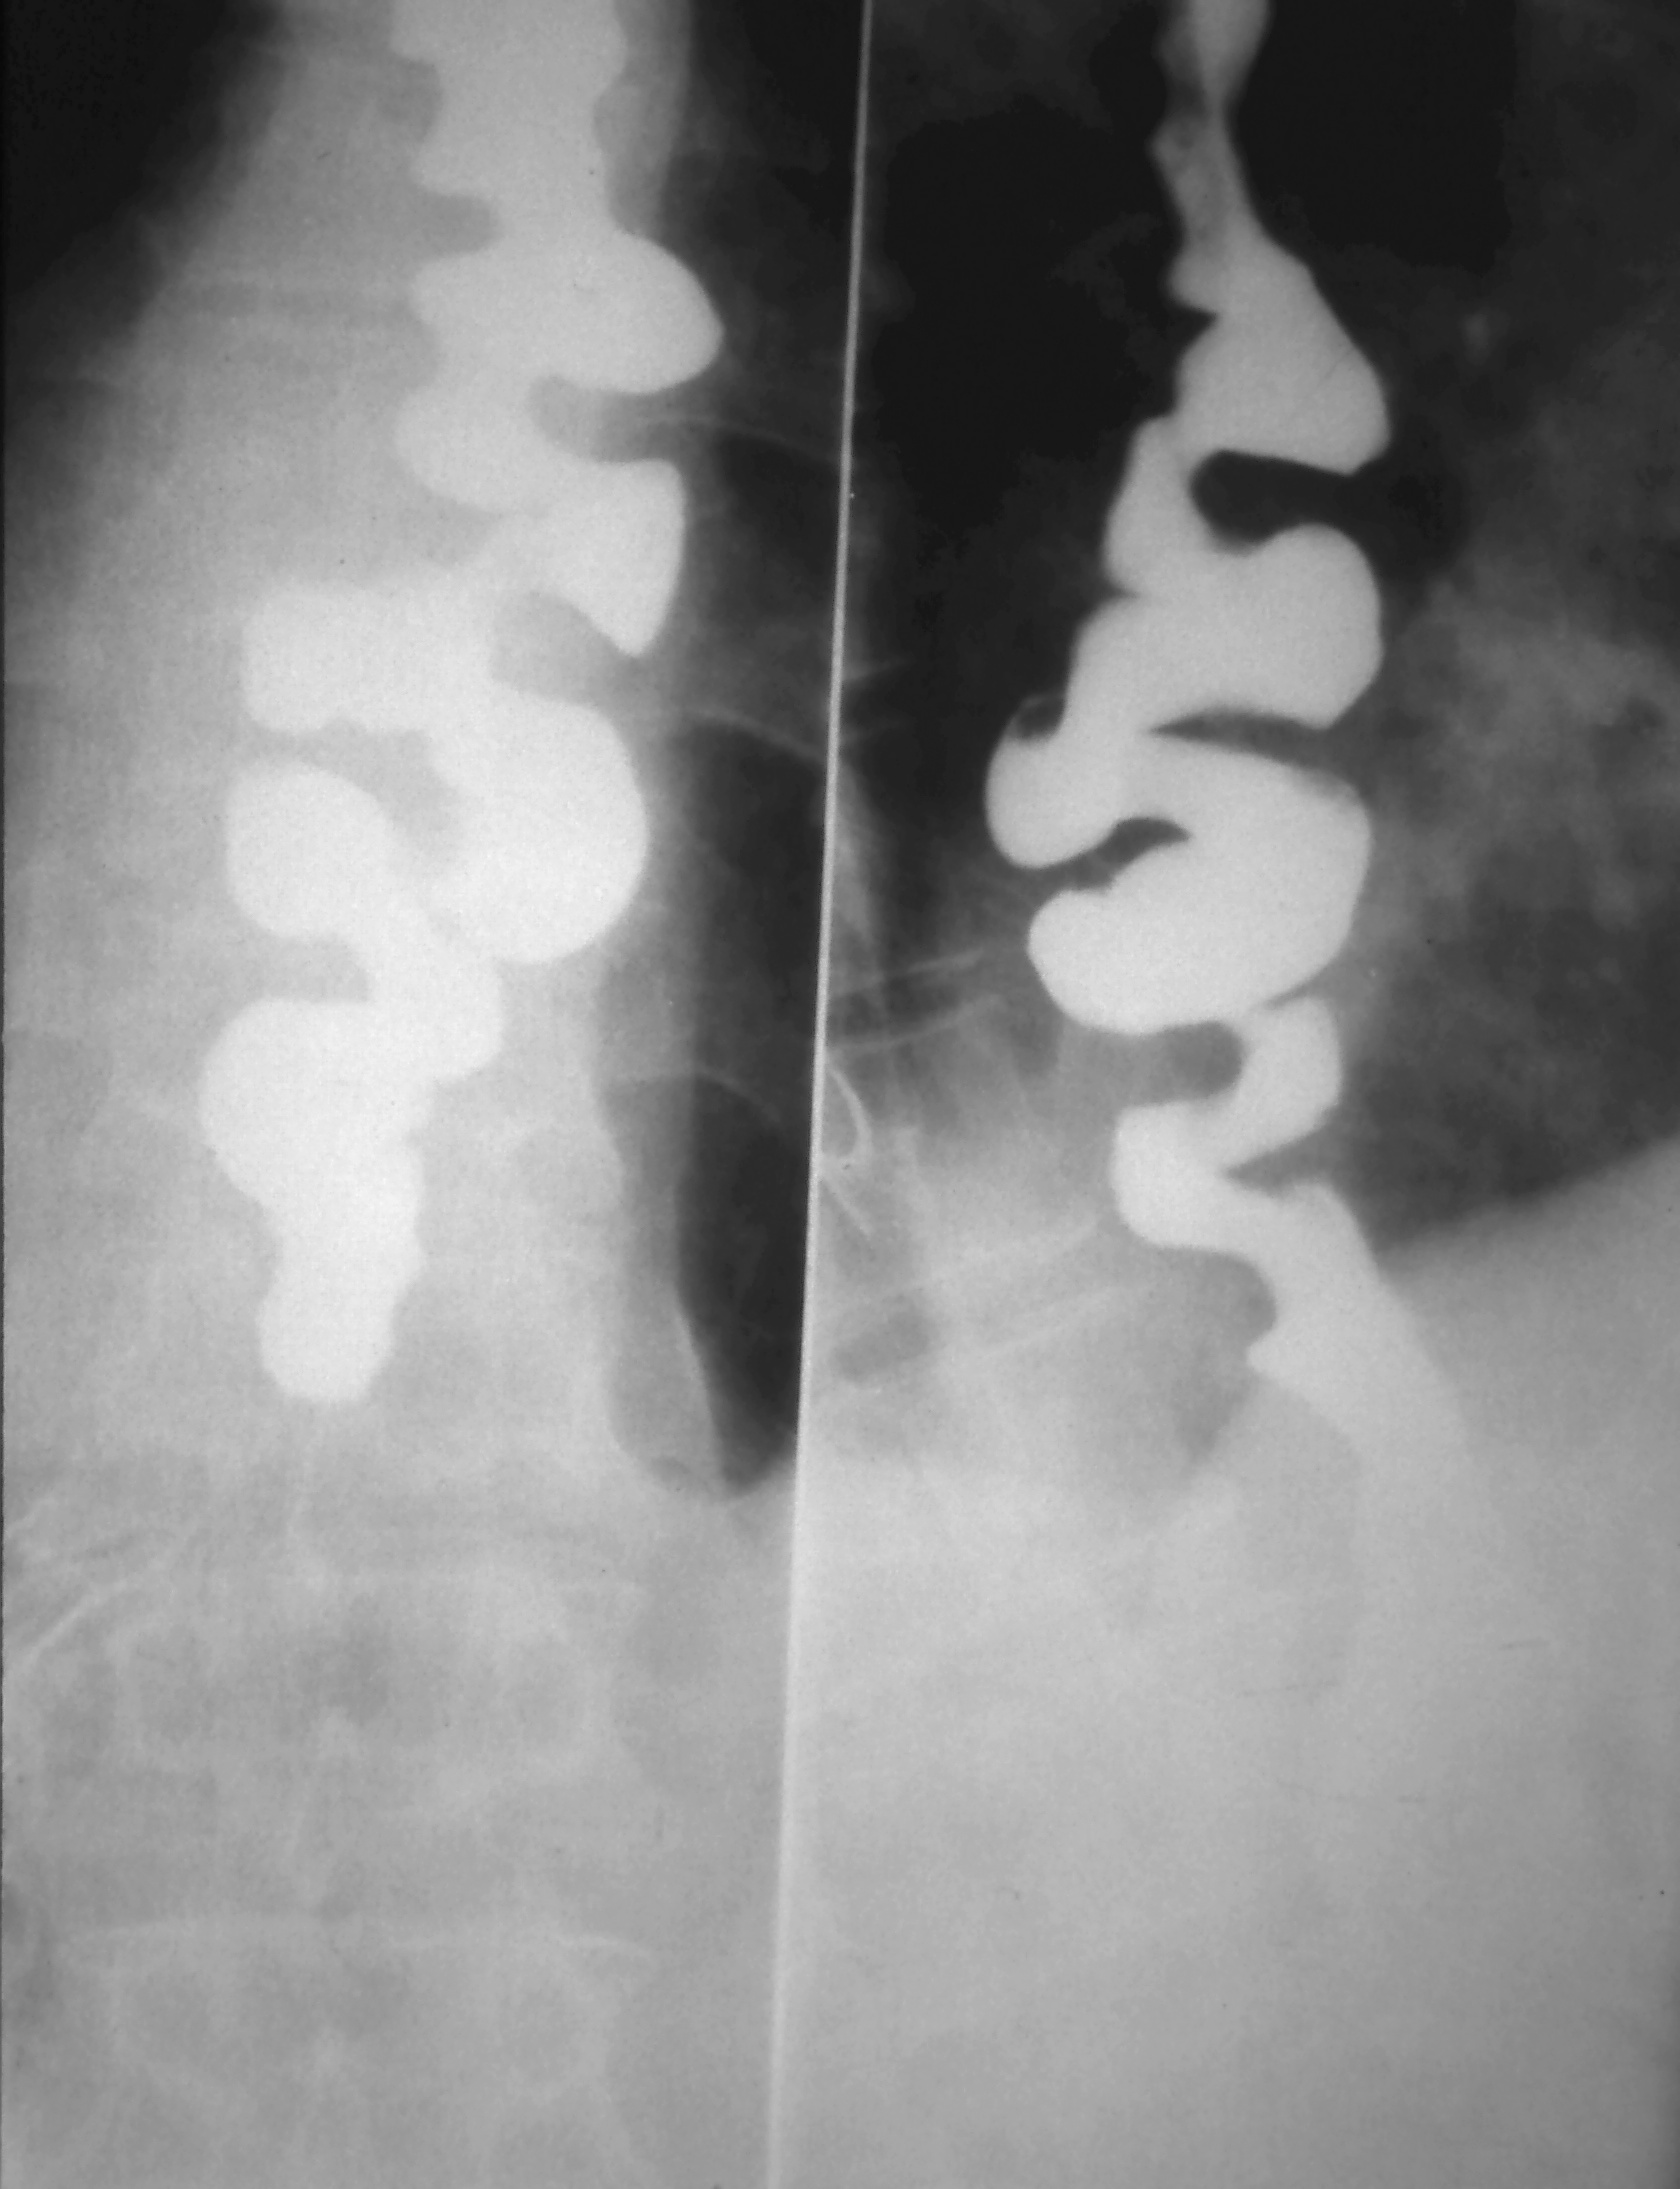

Diffuse esophageal spasm (DES). A, Spot film of esophagus in patient

Diffuse esophageal spasm (DES). A, Spot film of esophagus in patient Corkscrew Esophagus Vs Nutcracker Esophagus  What is the difference between nutcracker esophagus and diffuse esophagus spasm or corkscrew esophagus? This topic will review the pathophysiology, clinical features, diagnosis, and management of the following disorders of. Corkscrew esophagus makes the esophagus appear crooked or twisted. It can cause difficulty swallowing and chest pain. It is quite a rare. Jackhammer esophagus, or hypercontractile peristalsis, is an esophageal. Corkscrew Esophagus Vs Nutcracker Esophagus.